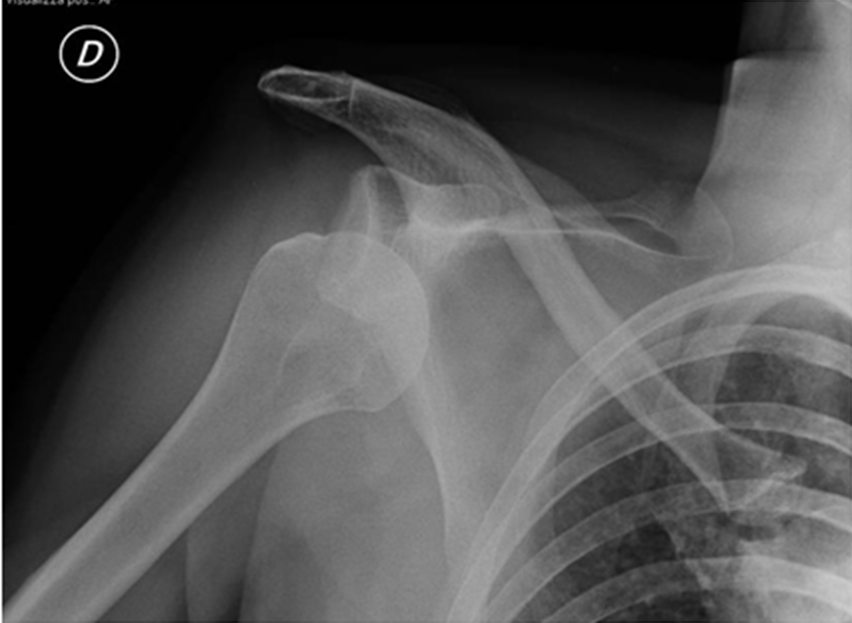

Standard x-rays are necessary prior to shoulder reduction. Examinations useful to confirm diagnosis and for surgical staging are computerized axial tomography (CT) and magnetic resonance imaging (MRI) scans. CT shows conformation, joint relations and possible proximal humerus and glenoid surface bone damage and more specifically if there are fractures or bone fragments. MRI gives more complete information for connective tissue tears and muscle trophism. In selected cases, to obtain a clearer definition and image of the damaged structures and areas adjacent to the joint both CT and MRI can be performed using contrast dye injected directly in the joint.

The surgical technique chosen depends mainly on: age, frequency of the dislocations or if these are absent, duration of shoulder pain and degree of impediment during sports or working activities, muscle structure, level of weight-bearing during work, sports practiced as professionals or amateurs. It is important to rule out the presence of fractures associated to the dislocation, for this CT or MRI are very useful.